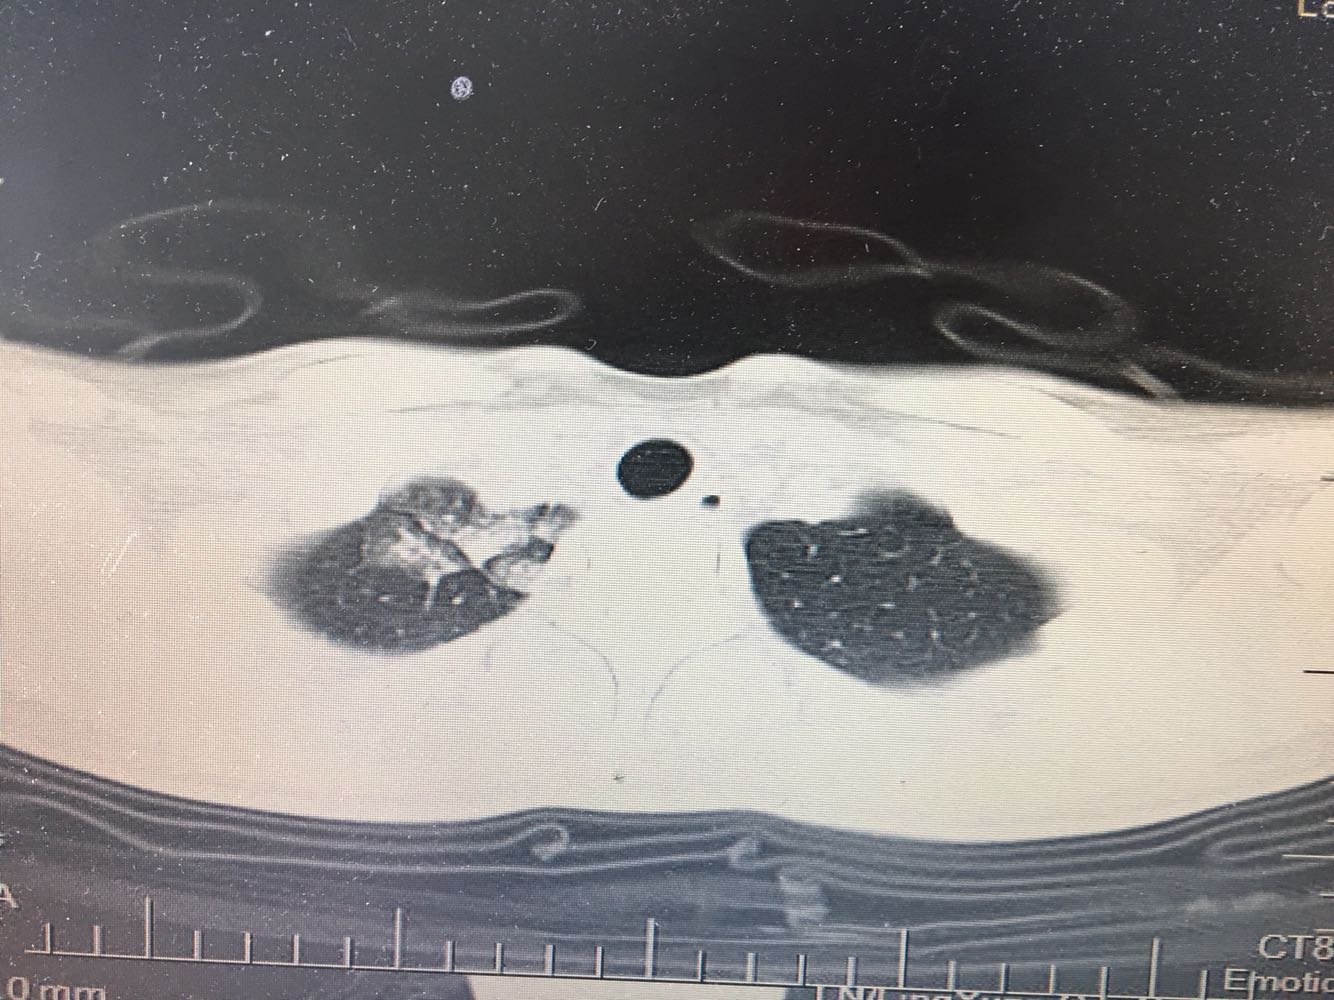

女,26岁,咳嗽1周,咳痰不畅,咽喉痒,口服阿莫西林无好转,昨日发热,体温38.5摄氏度,于门诊查肺CT后以肺炎收入院,病来无盗汗,无咳血,无消瘦及乏力,无头痛,无肢体酸痛,饮食睡眠可,二便正常

支原体肺炎?肺结核?

支原体抗体1:160,结核抗体弱阳性。支原体肺炎个别可见上叶病变,该患无结核中毒症状,考虑支原体肺炎可能性大,但肺尖为结核好发部位,需要抗炎治疗后复查观察疗效。